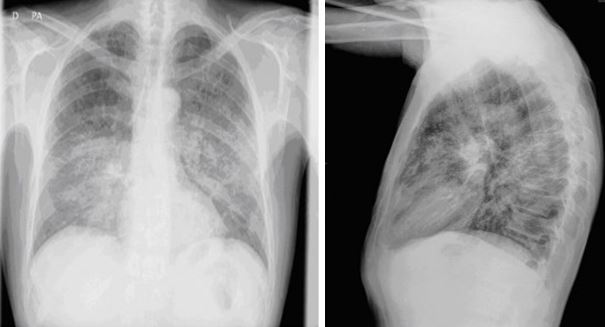

Paciente mujer de 54 años fumadora de un paquete al día desde hace 40 años, con hipotiroidismo primario y síndrome depresivo. Seguida en consultas externas de Ginecología por citología cervical compatible con Lesión epitelial escamosa de bajo grado (LSIL). En el año y medio previo al actual ingreso tuvo 4 episodios de infección respiratoria requiriendo ingreso hospitalario en uno de ellos. Ingresa en UCI por cuadro de disnea, dolor de características punzantes en hemotórax derecho e irradiado a espalda de características pleuríticas. No tos ni expectoración, no fiebre ni sensación distérmica, no ortopnea ni DPN. Refiere en las 3-4 semanas previas un síndrome general con pérdida de peso de 5 Kg. A su llegada a Urgencias la paciente está hipotensa, taquipneica y en gasometría presenta datos de hipoxemia con acidosis metabólica (pH 7,31; pO2 67; pCO2 50; HCO3 2,4). En análisis general destaca: Hb 9,5 g/dl; Leucocitos 8100 cel/ml; Linfocitos 990 cel/ml; Urea 70 mg/dl; Cr: 2,91 mg/dl; Procalcitonina: 25,33 ng/ml. En Rx Tórax se observa una condensación neumónica en LSD (Ver figura). En los hemocultivos crecen cocos gram positivos en diplos y cadenas cortas. En lavado broncoalveolar se observan quistes y trofozoitos característicos. Se realiza test serológico específico que resulta positivo.

CASO CLÍNICO DEL MES DE DICIEMBRE (Cerrado. Ver solución y lista de ganadores) Paciente de 46 años sin antecedentes médico-quirúrgicos de interés, ex-fumador desde hace un año sin otros hábitos tóxicos. Originario de Venezuela lleva residiendo en España tres meses cuando consulta en Junio 2011 por un cuadro de una semana de evolución caracterizado por una disnea progresiva hasta hacerse de pequeños esfuerzos, con tos ocasional no productiva y rinorrea blanquecina, fiebre de 39º, sin dolor torácico ni edema en extremidades inferiores. Refiere que desde un año antes presenta anorexia y pérdida de peso importante. En la exploración física destaca un aceptable estado general, TA: 98/70, Tª 36,2º, Pulso 107 lpm, taquipneico a 20 rpm con Saturación basal del 93%. En cara presenta una dermatitis seborreica severa, en la lengua se observan placas blanquecinas en los bordes compatibles con una leucoplasia vellosa, en la auscultación pulmonar se objetiva una hipoventilación generalizada y el paciente tiene varios tatuajes además de lesiones cutáneas de rascado y pústulosas en piernas y tórax. En la analítica destaca una linfopenia de 900 cel/µL y Hb de 12,9 g/dl y en la gasometría arterial pH 7,48; pO2 53 y pCO2 31. En la radiografía de tórax se describe una enfermedad intersticial difusa de predominio perihiliar que se extiende hacia las regiones subpleurales y es confluente en algunas areas. (Figuras 1 y 2). Se solicita una serología de VIH y una broncoscopia de cuyos resultados estamos pendientes.

Paciente de 43 años, ExADVP, VIH positivo diagnosticado en 1992, categoría A3. Sin TAR por decisión propia desde el año 2006. Último control realizado en Julio 2010 con CD4 de 10 células/µL que además supone el nadir del paciente, y RNA-VIH de 195.920 cop/ml. Hepatitis crónica VHC genotipo 3 tratada y con respuesta virológica sostenida. Fumador de un paquete al día. Consulta en Septiembre de 2010 por cuadro de 7 días de evolución caracterizado por sensación febril, astenia y tos escasamente productiva que es tratado inicialmente por su médico de cabecera con amoxicilina-clavulánico sin mejoría. En la exploración física destaca un aceptable estado general, temperatura de 38,2o C, hemodinamicamente estable, eupneico, sin adenopatías palpables, algún roncus disperso en la auscultación pulmonar; resto de la exploración sin datos relevantes. En la analítica destaca una linfopenia de 870 cel/µL, Hb de 11,3 g/dl y Na de 134 mEq/L. En la radiografía de tórax se describe un patrón intersticial en hemitórax derecho de predominio en LI y LM (Figura 1). En el TAC toracoabdominal se visualiza un conglomerado adenopático en hilio pulmonar derecho de unos 4 cm con adenopatías confluentes necróticas. También se observan otros ganglios más pequeños a lo largo de la cadena paratraqueal y traqueobronquial derecha y en la región subcarinal, la mayor parte de ellos con necrosis central y realces capsulares. No otras localizaciones.

Extensos cambios enfisematosos. (Figura 2). En el esputo inducido la auramina y el cultivo posterior para micobacterias son negativos y el antígeno de Pn jirovecii también resulta negativo.